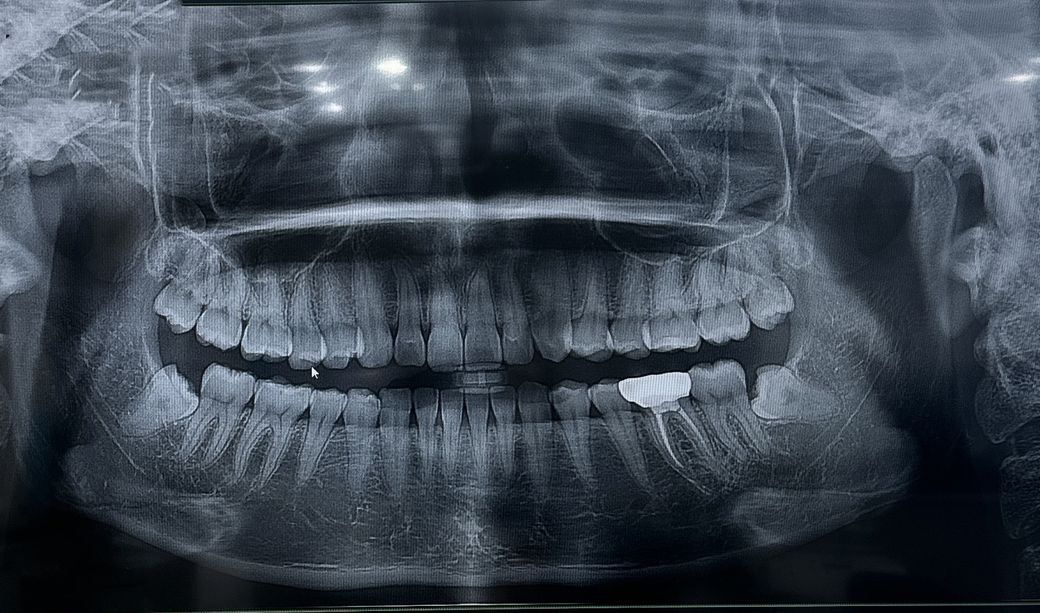

2020년도에 어금니에 크라운치아를 씌웠습니다. 최근 크라운 씌운 이에 통증이 생기고 뜨거운 음식이나 차가운 음식, 씹을 때 통증이 더 많이 느껴져요. 병원에서는 엑스레이 찍고 엑스레이상 문제가 없는 데 간혹 높낮이가 안맞아 아픈 경우가 있다고해서 살짝 갈았음에도 통증이 지속됩니다 ,,

• 1번 째 사진